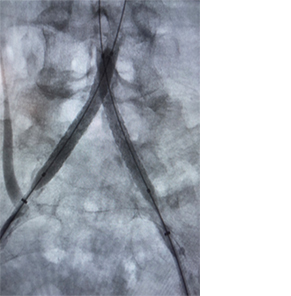

• result.png

Résultat

Images avec l’aimable autorisation du Dr Norby.

Les résultats individuels peuvent varier.